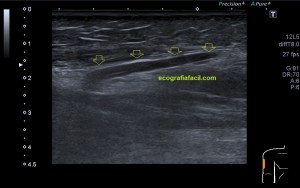

En este breve post te voy a presentar unas imágenes muy bonitas de una vesícula, en una paciente que acude a la cita de ecografía por sospecha de patología a ese nivel, con molestias anodinas e inespecíficas en el contexto de un estudio de su especialista de digestivo.

Observa las imágenes y luego te explico los hallazgos:

Cuando hice el corte longitudinal de la vesícula pude ver hasta tres patologías distintas, una adeomiomatosis (sin artefacto en cola de cometa), una litiasis vesicular y barro biliar, 2,3 y 4 respectivamente.

La adenomiomatosis, como un aumento de la ecogenicidad y el tamaño de la pared vesicular, la litiasis como una estructura hiperecogénica con sombra acústica posterior y el barro biliar, hiperecogénico rellenando toda la estructura ovoidea de la vesícula.

El cuello vesicular estaría afectado por la adenomiomatosis, el cuerpo por la litiasis y el barro ocuparía el fundas vesicular.